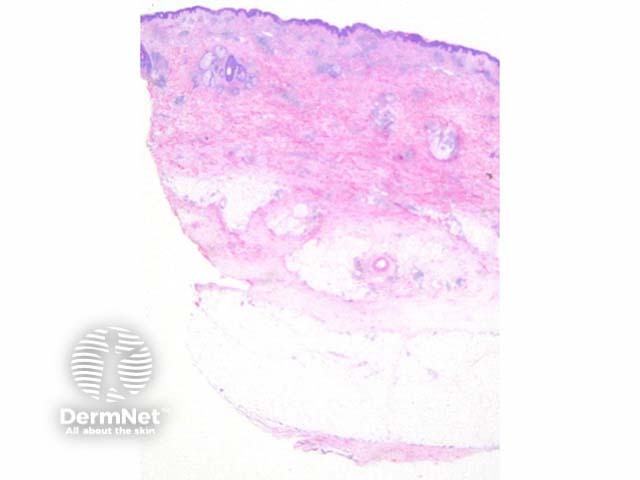

Scanning power view of Wells syndrome reveals a superficial and deep perivascular and interstitial inflammatory pattern (Figures 1 and 2). This can be seen to extend into the subcutaneous tissue (Figure 3) or even the underlying muscle. The inflammatory infiltrate is comprised of lymphocytes, histiocytes and abundant eosinophils (Figures 4,5 and 6). Degranulation of the eosinophils is seen forming flame figures (Figures 4 and 5). In this particular case extensive interstitial mucin is seen (Figures 4 and 5).

Figure 1